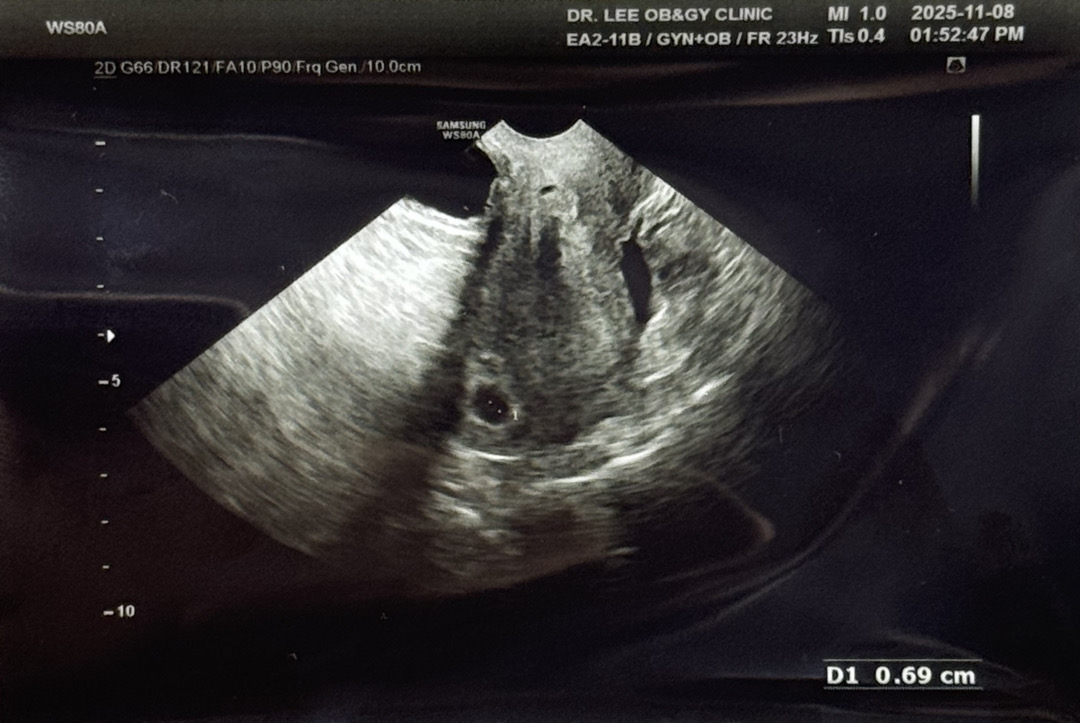

아기집 보고왔어옹

막생 기준으로 11/8(토) 5주 4일차에 아기집 보고왔어요-! 난황은 입덧때문에 아기집이 뿌옇게 보인다고 못보고 11/18(화)에 심장소리 들으러 오라더라구요-! 지금은 점점 입덧이 시작되는느낌이에용